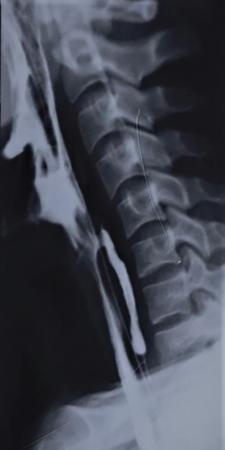

Clinical history

A 60-year-old male with history of chronic alcohol consumption and chronic weight loss and pain epigastrium presented to Radiology for USG. A finding on USG called for a barium meal and follow-through for academic purpose.

Key findings

Barium meal and follow-through spot image revealed widening of C loop of duodenum along with extrinsic compression on the antrum posteroinferiorly giving rise to classical ‘antrum pad’ sign. There was, however, no obvious mucosal irregularity seen. There is evidence of contrast hold-up.

Analysis and interpretation

The image showcases two classical signs in GI radiology which are the ‘widening of C loop of duodenum’ and the ‘antral pad sign’. Both the signs are typically described in masses of head of pancreas. A comment on the mucosal lining (regular/irregular) may give a pointer towards the mass being malignant. However, this is a nonspecific sign giving indication of a mass effect and has a variety of differentials. The final diagnosis is reached with the help of cross-sectional imaging and/or endoscopy/biopsy. CECT abdomen in this case confirmed it to be a case of carcinoma pancreas (Fig. 7.4.6.1).